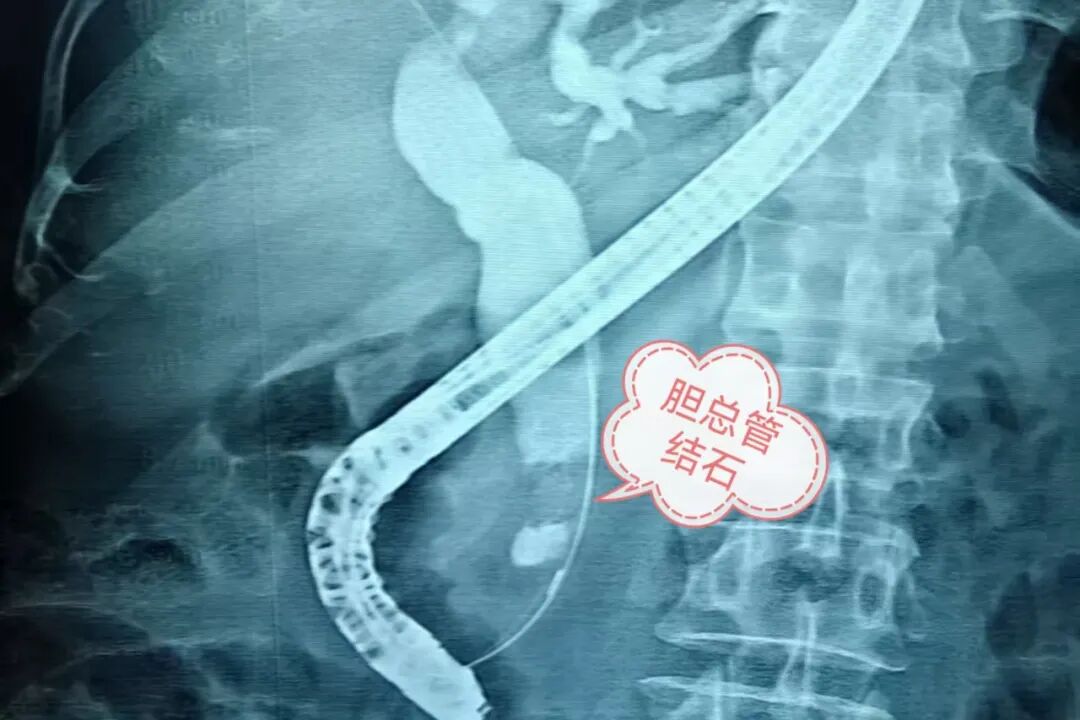

据介绍,该名老年男性患者因“腹痛5小时”于6月20日凌晨1时许紧急入院。询问病史了解到,既往6岁时(60年前),患者曾行胆道外科手术。入院时患者腹痛剧烈,上腹部压痛、反跳痛明显。入院后消化内科立即完善相关检查,结果显示:天门冬氨酸氨基转移酶220.9(U/L)、谷氨酰胺转移酶955.3(U/L)↑;总胆红素 82umol/l,直接胆紅素56.8(uma1/L)↑。腹部CT提示:胆总管下段结石并肝内外胆管扩张、胆囊增大。结合检查患者诊断为胆总管结石并急性胆管炎,且CT可见胆管系统扩张,提示有胆总管梗阻。此时,患者皮肤巩膜黄染,血常规感染指标明显升高(白细胞 22.78(10*9/L),中性粒細胞94.1% ),提示感染严重,若不及时去除患者的胆总管结石、解除胆总管梗阻,按照病情发展趋势及预后,患者将很快出现化脓性胆管炎,危及生命。

患者的救治刻不容缓!消化内科ERCP团队与介入室紧密协作,以最快速度安排患者行急诊ERCP取石术。术中,患者的情况给ERCP团队带来重重挑战,进镜达患者胃底时发现胃腔有大量食物潴留,患者幼年胆道手术史更让手术难度大大提升。叶营主任医师借娴熟精湛的内镜技术,沉着应对、精准操作,成功克服难题,顺利完成ERCP取石治疗,解除了患者的胆道梗阻。术后患者恢复良好,各项指标逐步恢复正常,顺利出院。出院前,患者以赠送锦旗的形式来表达对消化内科团队的诚挚谢意,同时也是对消化内科团队技术和服务的充分肯定。